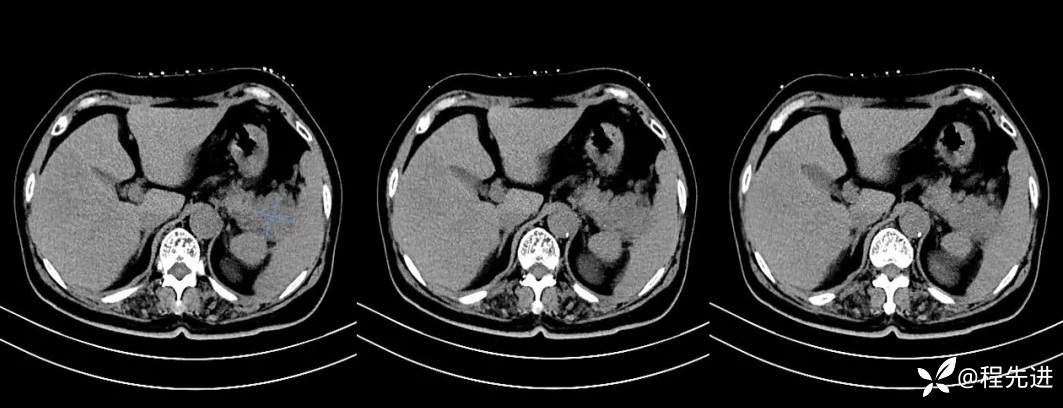

【现病史及既往史】:体检发现胰尾部肿块4年,当时手术病理提示异常增生性病变,现发现右侧顶部包块,逐渐增大,无明显感觉不适

影像检查: